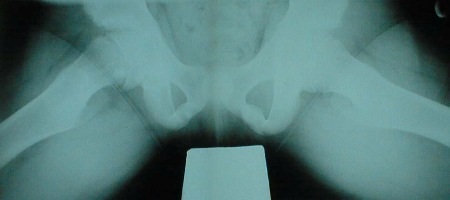

- radiografia dos quadris (incidências em posição de rã necessárias):

epifisiólise proximal do fêmur

Primeira investigação

- radiografia dos quadris:

quadris deslocados/displásicos